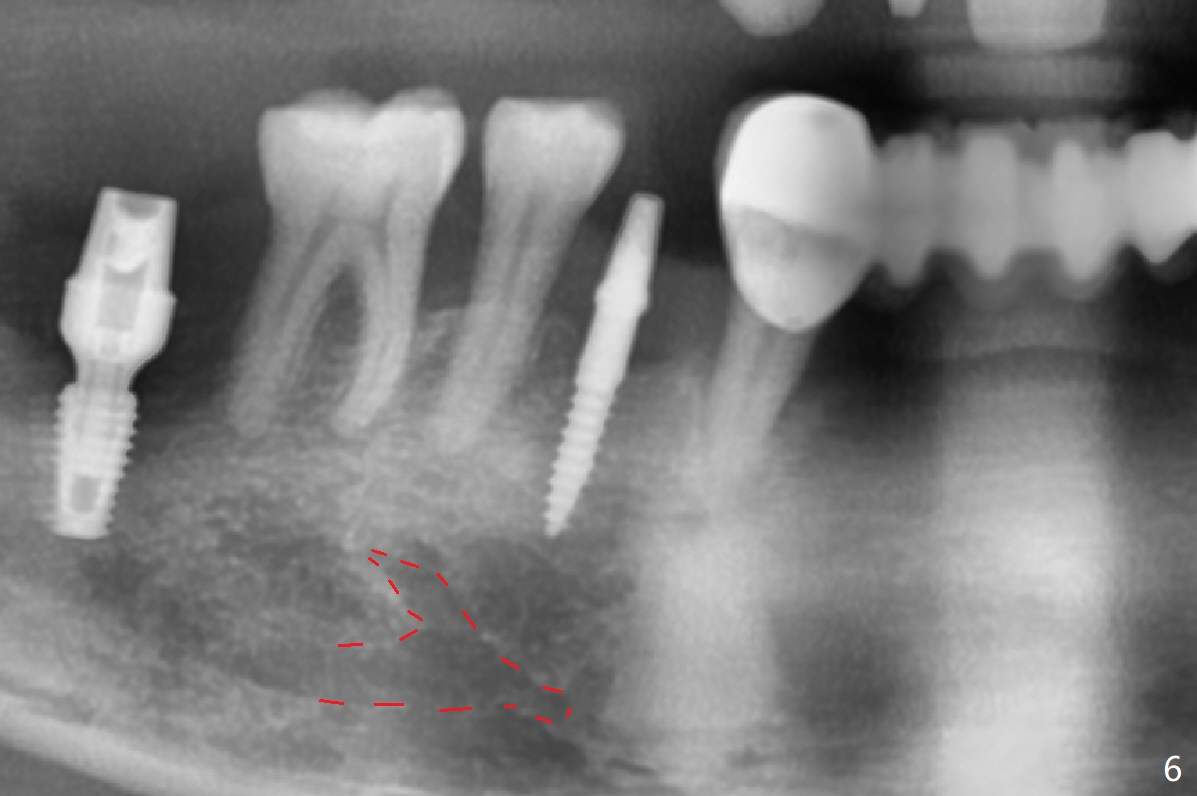

When flaps are raised at #28, the ridge appears to be narrow. Severe ridge resorption occurs 1-2 years post exfoliation. After ridge reduction, osteotomy is initiated mesially (Fig.1 (broken drill as a parallel pin)). A new osteotomy is going to be initiated as indicated by a blue line in Fig.1. It is done close to what is expected (Fig.2). When a 2.5x10(4) mm 1-piece implant is placed <20 Ncm, a major concern is where the Mental Loop is. To answer the question, intraop CBCT is taken (Fig.4). It appears that the ridge has not resorbed. If palpate more lingually (Fig.4 white <), the ridge would be found not so narrow. Preop and intraop panoramic X-ray film show sufficient bone height at the site (Fig.5,6). Low torque may be associated with low postop bone resorption, but it will take long to restore the implant.